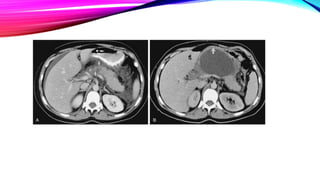

• -CAT: Clasifica gravedad de la pancreatitis

Glándula aumentada de tamaño, de bordes mal definidos,

heterogeneidad del parénquima, presencia de colecciones líquidas

PANCREATITIS AGUDA

PANCREATITIS AGUDA DIAGNÓSTICO • -Radiografía:Datos inespecíficos(colon cortado, halo perirrenal, calcificaciones pancreáticas,etc) • -Ecografía: para descartar etiologías de la vía biliar • Páncreas agrandado y deformado. • -CAT: Clasifica gravedad de la pancreatitis Glándula aumentada de tamaño, de bordes mal definidos, heterogeneidad del parénquima, presencia de colecciones líquidas